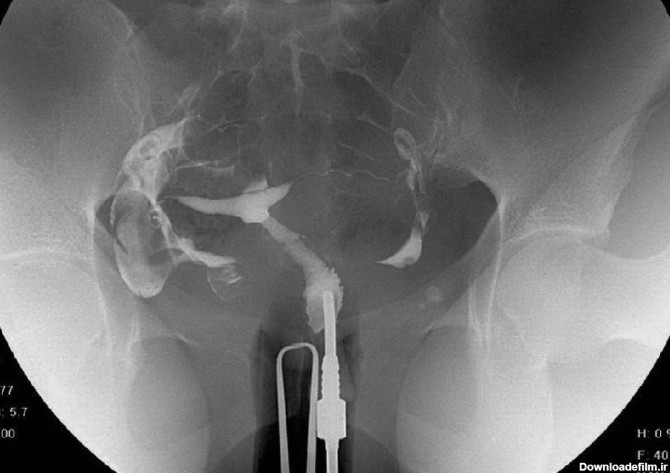

هزینه عکس رنگی رحم با بیمه هایی نظیر بیمه تامین اجتماعی، بیمه خدمات درمانی، بیمه نیروهای مسلح و بیمه تکمیلی درج شده است.

الزاما در عکسبرداری رنگی رحم فرد بیهوش نمیشود، بنا به صلاحدید پزشک و انتخاب بیمار تصمیمگیری میشود که آیا بیمار تحت بیهوشی قرار گیرد یا خیر؟